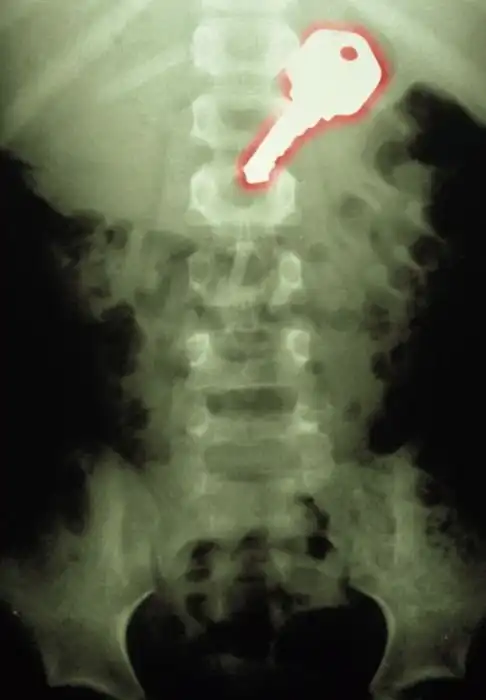

Жуткие рентгеновские снимки

Порой даже не верится, с какими странными и необычными повреждениями в травматологию могут поступить пострадавшие. Всю эпичность профессии врачей травматологии могут с легкостью подтвердить рентгеновские снимки.

на последнем, по моему бутылка

о теперь пригляделся увидел)